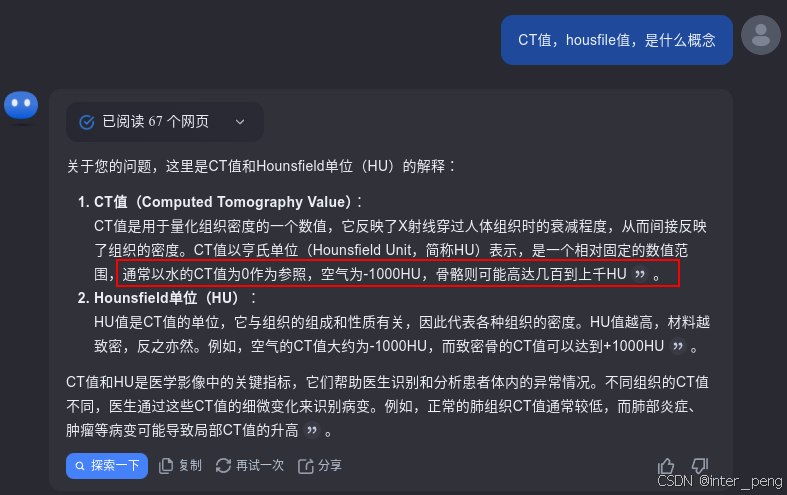

关于CT值的概念,可以通过咨询kimi助手了解到,它主要就是反映人体内组织的密度。密度越小,CT值越小;反之,则CT值越大。由于肺部里面,主要是充满着很多的空气,因此,如果是包含胸肺的序列,它的影像的最小值,一般是-1024(空气的CT值);而由于胸肺区域,还有肋骨,所以它的影像的最大值,一般是1000+以上(骨骼的CT值)。

其实,之所以这个有问题的序列,在我们的软件产品中黑屏,而在slicer, 或其他的一些dicom viewer里面能够正常展示。是因为,这些软件,它们会根据这个序列的灰度范围,而自动调节显示时使用的窗宽窗位。而我们的软件,由于是给特定部位使用的,所以里面有一个默认的窗宽窗位,就像第一幅图中展示的, ww = 150, wl = 90.